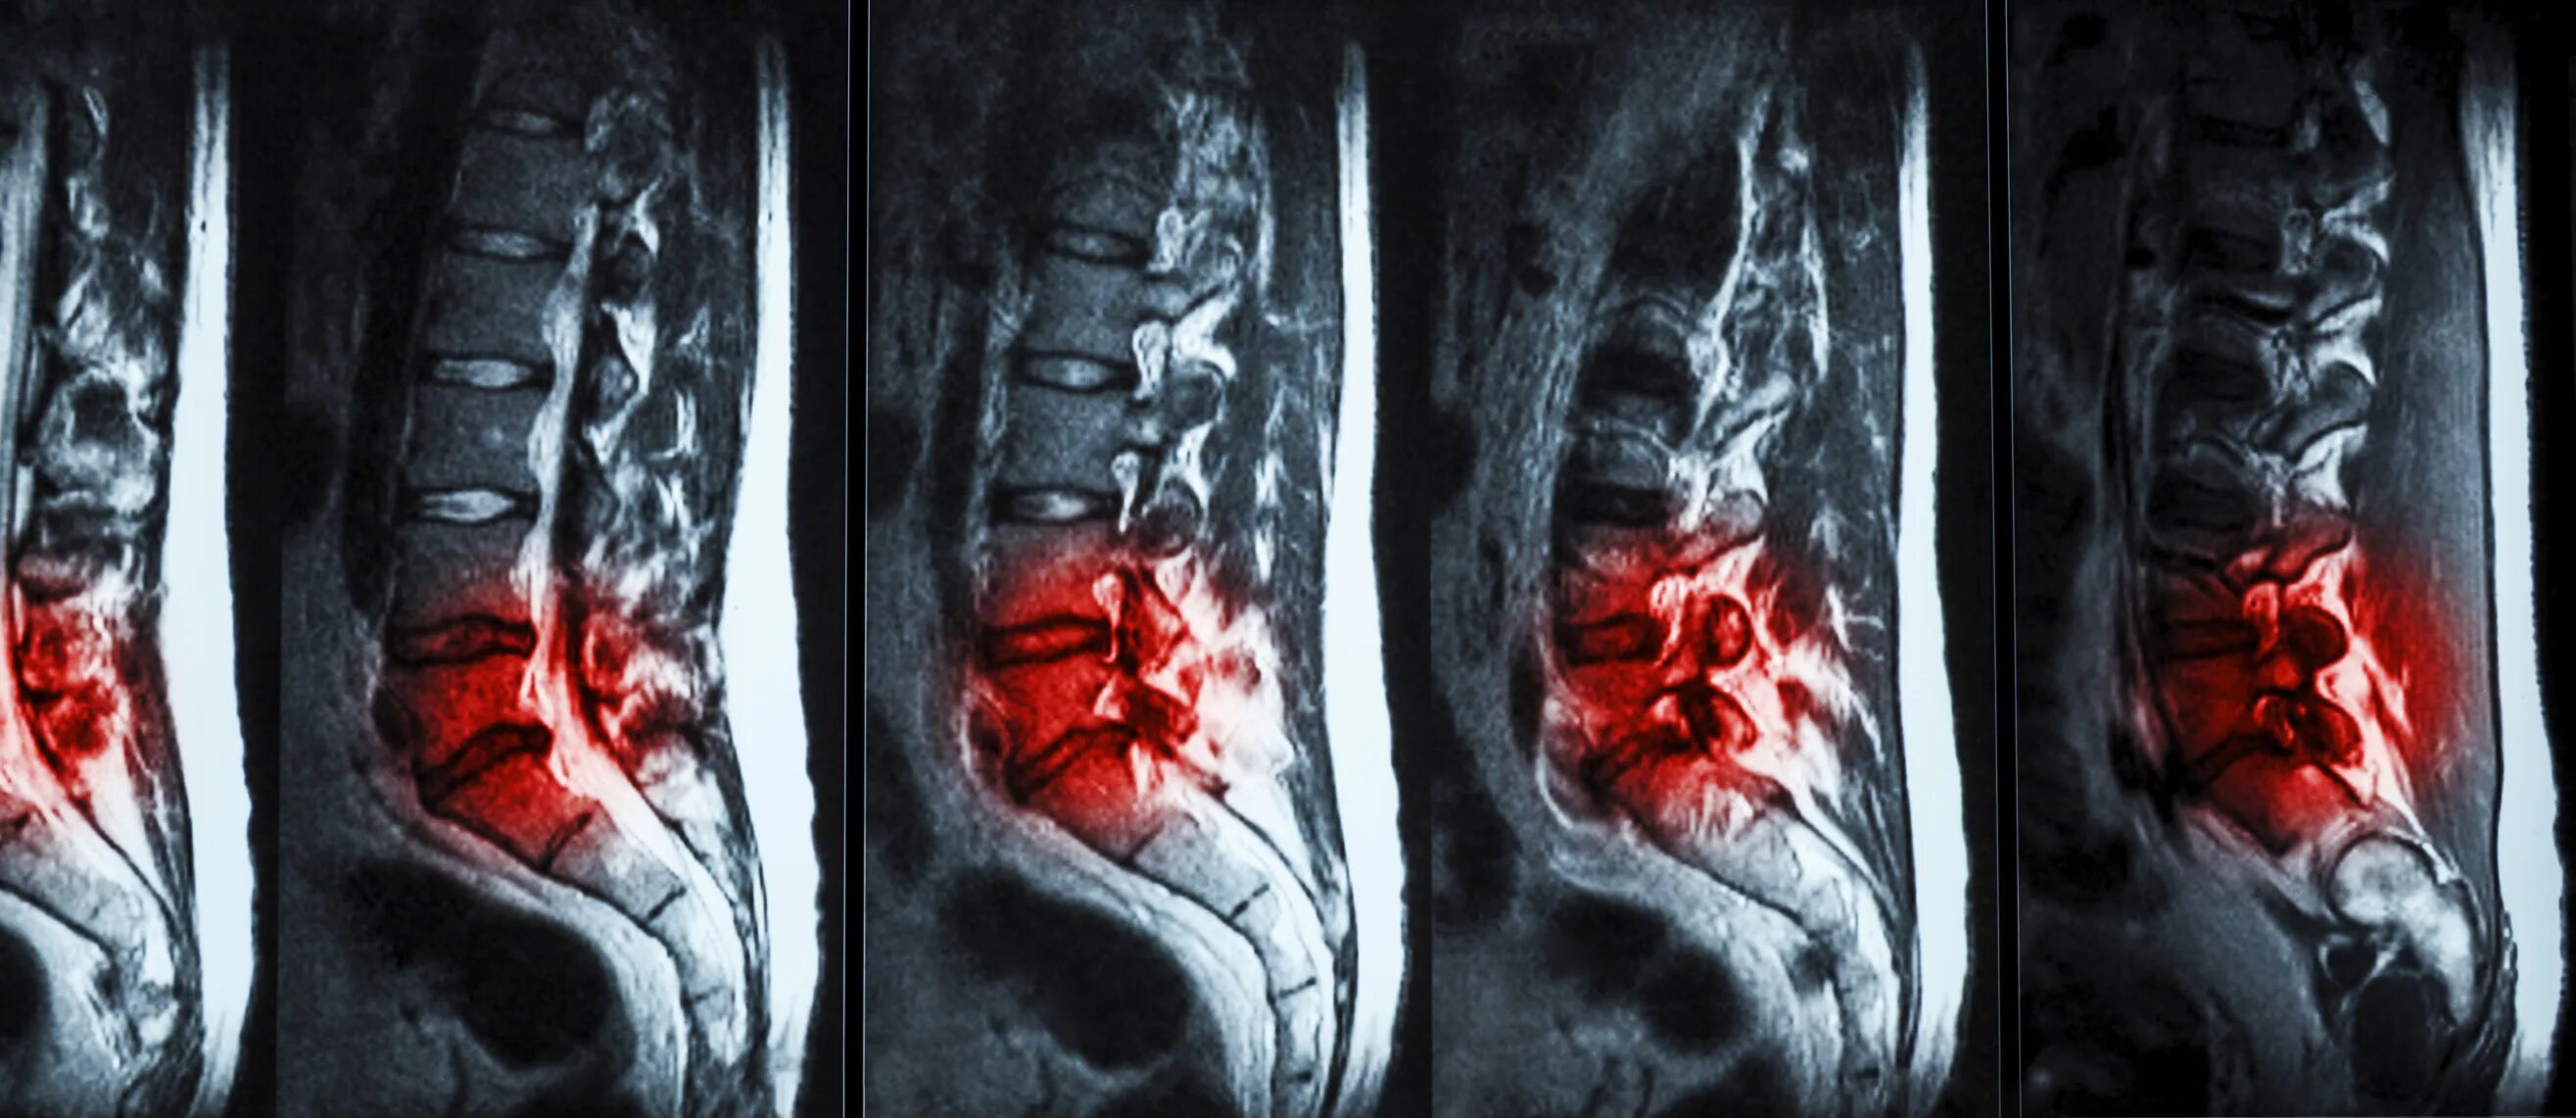

Мрт или кт позвоночника при болях